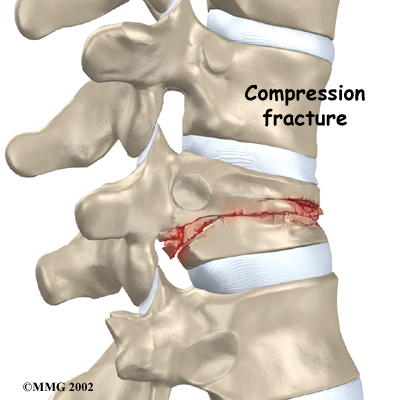

Compression fractures are the most common type of fracture affecting the spine. A compression fracture of a spine bone (vertebra) causes the bone to collapse in height.

Compression fractures cause this section of bone to collapse. When the fracture is due to osteoporosis, it usually occurs in the lower part of the thoracic spine, near the bottom of the rib cage.

Strong, healthy bones are able to withstand the forces and strains of normal activity. Compression fractures in the spine happen when either the forces are too great or the bones of the spine aren't strong enough. The vertebral body cracks under pressure. Fractures from forceful impact on the spine tend to crack the back (posterior) part of the vertebral body. Fractures from osteoporosis usually occur in the front (anterior) part of the vertebral body.

Spine trauma can produce mild or severe compression fractures. Compression fractures from trauma usually involve high forces that impact the spine when it is bent forward. This is typically what happens when a person falls onto the buttocks or strikes his head on the windshield in a car accident. Again, these traumatic fractures usually affect the back part of the vertebral body.